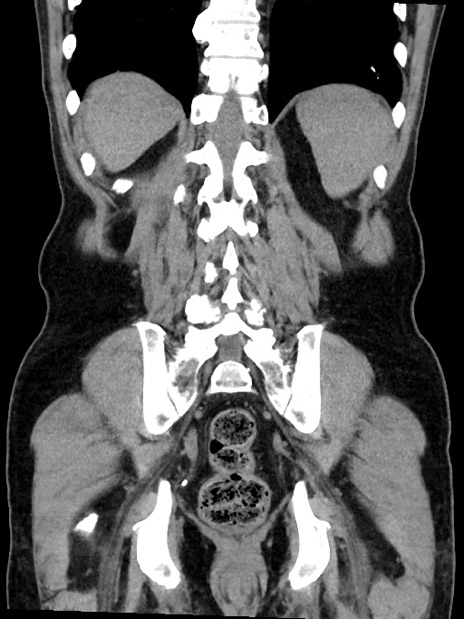

症例35(冠状断像)

【症例】70歳代 男性

【主訴】腹部膨満、嘔吐

【現病歴】昨日より腹部膨満感出現。本日増悪し、仙痛出現。嘔吐あり、受診。

【既往歴】糖尿病、胆摘後

【身体所見】BP 149/80mmHg、HR 74/min、BT 35.9℃、腹部:膨満、軟、圧痛なし。腸雑音減弱あり。上腹部正中切開瘢痕あり。

【データ】WBC 13500、CRP 1.72